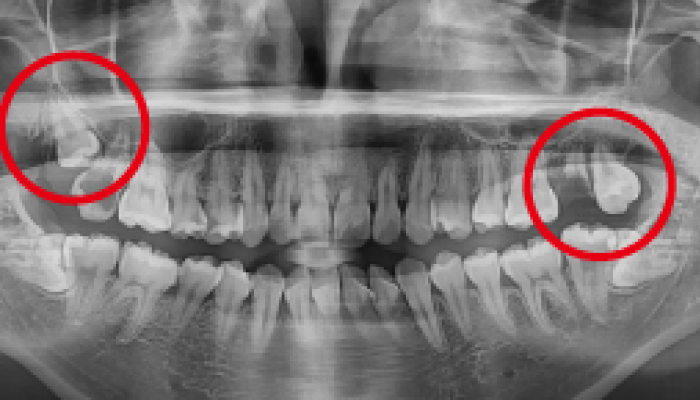

Before

로그인 후 이용해주세요

After

매복 사랑니 발치

이OO님 전후사진 / 치료 기간 : 30분 / 당일 사랑니 발치

Before

로그인 후 이용해주세요

After

매복 사랑니 발치

이OO님 전후사진 / 치료 기간 : 30분 / 당일 사랑니 발치

-

Before

로그인 후 이용해주세요

After

매복 사랑니 발치

심OO님 전후사진 / 치료 기간 : 30분 / 당일 사랑니 발치

-

Before

로그인 후 이용해주세요

After

매복 사랑니 발치

서OO님 전후사진 / 치료 기간 : 30분 / 당일 사랑니 발치

-

Before

로그인 후 이용해주세요

After

매복 사랑니 발치

김OO님 전후사진 / 치료 기간 : 30분 / 당일 사랑니 발치

-

Before

로그인 후 이용해주세요

After

당일 사랑니 발치

이OO님 전후사진 / 치료 기간 : 30분 / 당일 사랑니 발치

-

Before

로그인 후 이용해주세요

After

매복 사랑니 발치

노OO님 전후사진 / 치료 기간 : 30분 / 당일 사랑니 발치